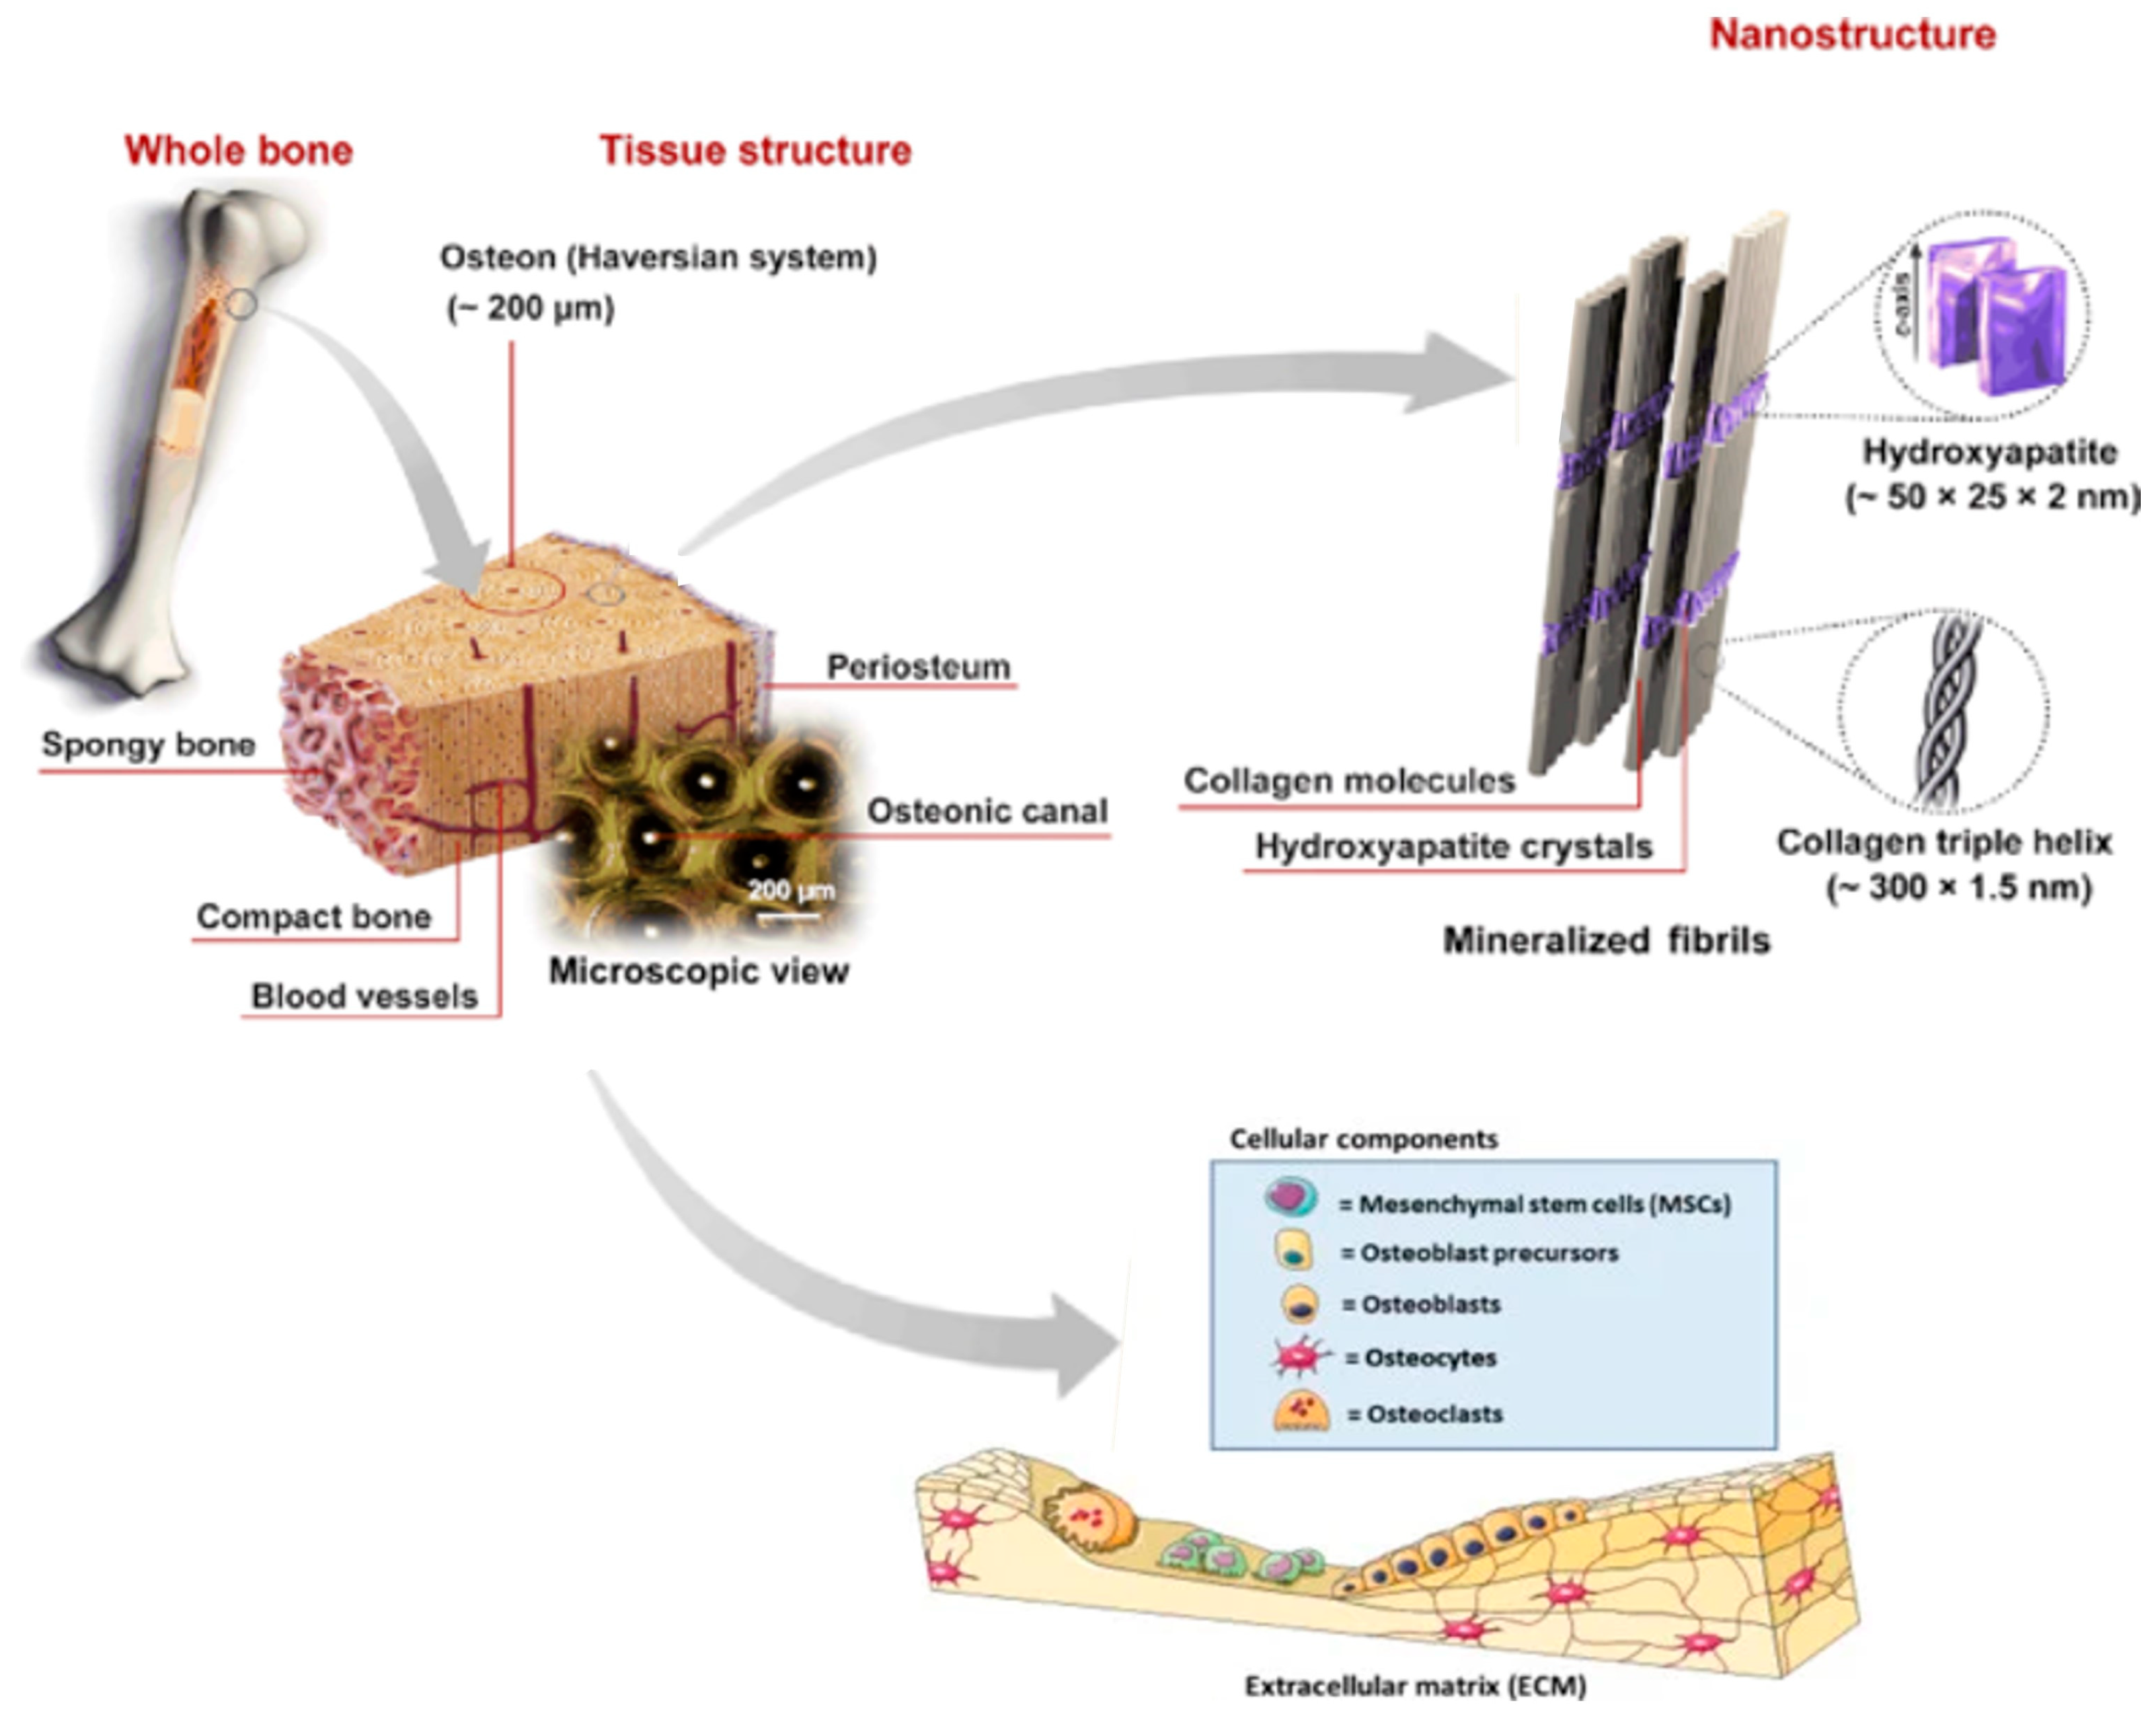

1. Introduction

3.2. Describing the Newly Formed Bone

3.2.1. Histologic Evaluation